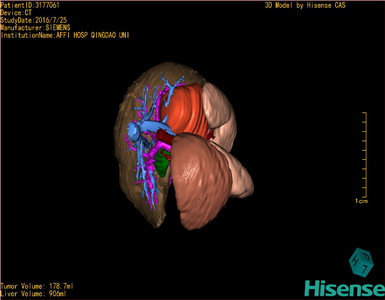

将0.625mm双源薄层CT资料的静脉期和动脉期Dicom格式文件导入海信CAS系统。

通过调节窗宽窗位调整CT序号,对肿瘤,肝实质,胆囊,下腔静脉,肿瘤,肝动脉、门静脉及肝静脉等进行三维重建;系统自动计算肿瘤体积和肝脏体积。

模拟手术操作,自动计算切除肿瘤体积。肝脏体积为906ml,肿瘤体积为178.7ml,肿瘤体积为肝脏体积的19.7%,通过比对6-9月正常肝脏体积为257.75±51.05ml,通过术前模拟手术,精准判断切除后剩余肝脏体积能耐受,避免肝衰竭发生。

术前三维重建:

重建图片